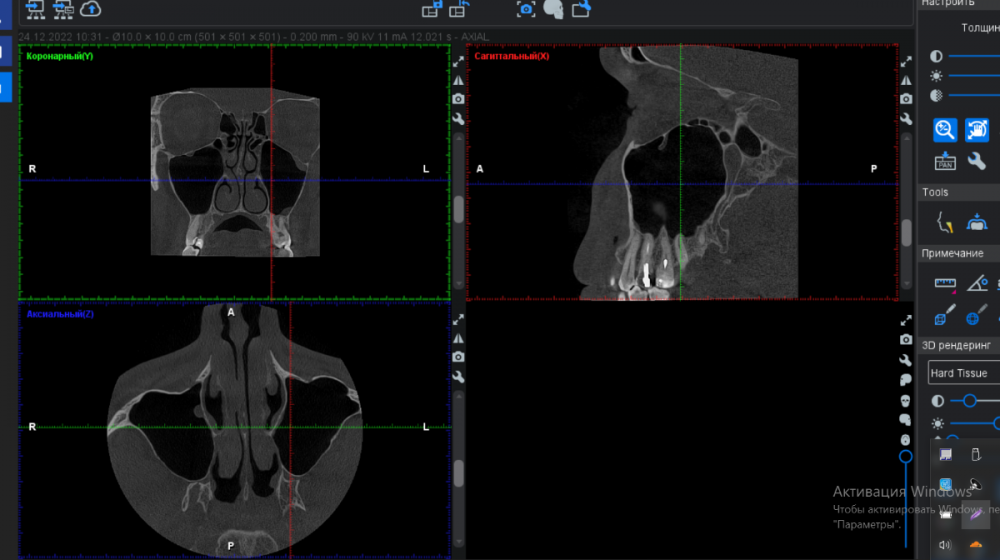

FISSMAN Опубликовано 8 апреля, 2023 Автор Поделиться Опубликовано 8 апреля, 2023 37 минут назад, IvanK сказал: покажите скриншоты Ссылка на комментарий

IvanK Опубликовано 8 апреля, 2023 Поделиться Опубликовано 8 апреля, 2023 пазухи выглядят хорошо 18,28 надо удалять 16,17 лечить 15 - периодонтит - может быть "виновником торжества" (причиной синусита, если обострится) 25, 26 - перелечивание и протезирование 6 часов назад, FISSMAN сказал: КТ сделал в самом начале лечения зубов. если это старый снимок, то имеет смысл делать новый.. 1 Ссылка на комментарий